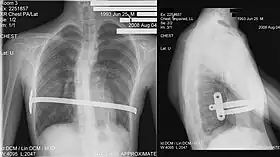

Nuss procedure

In 1987, Donald Nuss, based at Children's Hospital of The King's Daughters in Norfolk, Virginia, performed the first minimally invasive repair of pectus excavatum (MIRPE) [53] and presented it much later at a conference in 1997.[53][54][55]

His two-stage procedure, widely known as the Nuss procedure, involves slipping in one or more concave steel bars into the chest, underneath the sternum.[56]

The bar is flipped to a convex position so as to push outward on the sternum, correcting the deformity. The bar usually stays in the body for about two years, although many surgeons are currently moving toward leaving them in for up to five years. When the bones have solidified into place, the bar is removed through outpatient surgery.

Although initially designed to be performed in younger children of less than 10 years of age, whose sternum and cartilage is more flexible, there are successful series of Nuss treatment in patients well into their teens and twenties.[57]